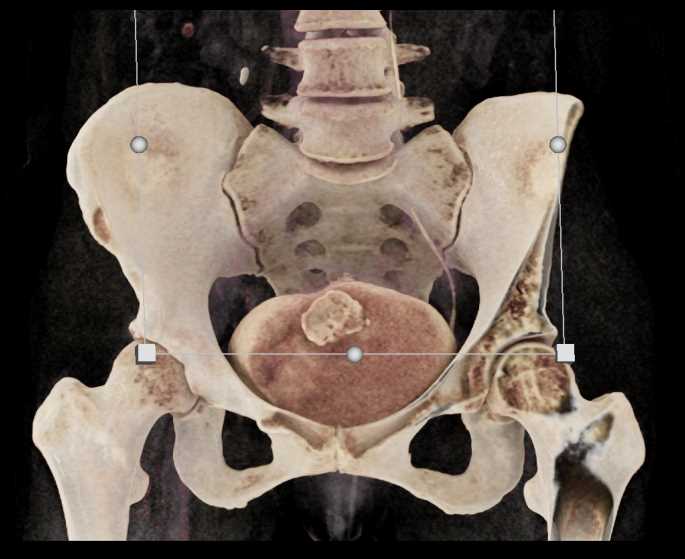

Urachal Carcinoma of the Bladder